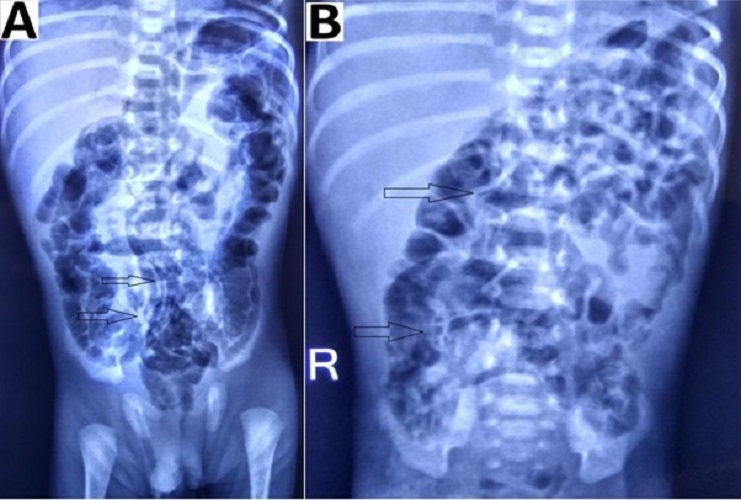

Figure 5

Radiographs showing (A) pneumatosis intestinalis with linear gas pattern (black arrow) and (B) bubbly gas pattern (black arrow).

Intestinal pneumatosis is a pathognomonic sign for NEC. According to different sources, detecting this sign in ultrasound varies between 13% and 100%, while in radiograms, it ranges from 20 to 95%.[21] A linear (crescent) gas pattern (Fig. 5) is a more specific sign than the bubbly (foamy) gas pattern.[15]

We detected fixed bowel loops in 3 patients (18%) pneumatosis intestinalis (Fig. 5) in 1 (6%), portal venous gas in 1 (6%), and massive ascites (Fig. 4) in 2 patients (12%) among the group B (with the absence of pneumoperitoneum). These percentages (findings) were relatively small in our study, but in presence of clinical signs, they contributed towards deciding to operate in our study. Thus collectively (clinico-radiologically), more than one sign according to Modified Bell’s staging was present in group B patients, i.e. 8 (50%) stage IIIA, 12 (75%) stage IIB, 1 (6%) stage IIA and 3 (18%) stage IA/IB.